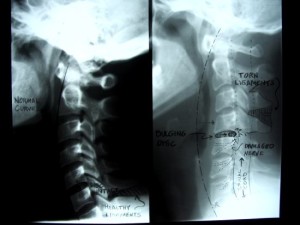

Whiplash

One of the most recognized injuries known for causing problems days or weeks later is whiplash. Also called Cervical-Acceleration-Deceleration (CAD), whiplash is a sudden forward motion of the neck that quickly snaps back into its original position, an injury that usually happens in rear collisions. There are four phases in a whiplash injury: Initial position, retraction, extension and rebound.

The initial position is where the neck was before the impact. Retraction occurs at the moment of impact;

there is a heavy loading of soft tissues. Extension comes next, where the neck and head slide forward, but not all the way due to the seat belt. The final phase is rebound, where the head and neck whip back. This injury puts a heavy strain on the spine and vertebrae. The resulting symptoms that may appear days later include back and neck aches, headaches, dizziness and sensory issues such as pins and needles, and tinnitus.